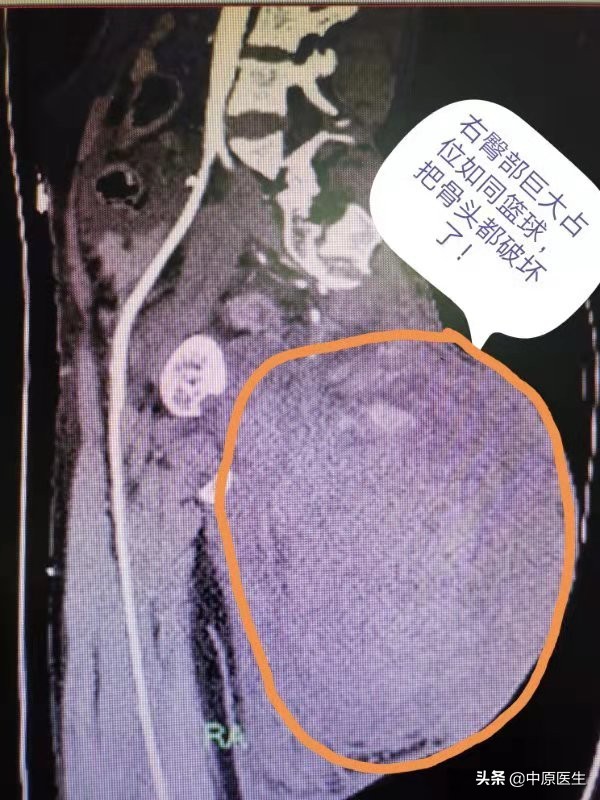

半夜急诊CT出来一看,证实肿瘤就是出血了,肿瘤早把附近骨头破坏了,真佩服这个母亲的忍受力!与家属充分沟通后,等待二女儿过来后行微创介入栓塞。

7月28日下午,患者与丈夫在郑州东区正在做装修工作时,突发剧痛,屁股上的肿瘤也跟吹气球似的瞬间增大,由足球大小变成了篮球大小,紧接着就是头晕、心慌,不能站立也不能坐下,只能痛苦的趴在地上。

急诊科医生看到这种情况考虑是肿瘤内部出血了,把肿瘤吹气球似的撑起来了,张力非常大,随时都有爆掉的可能似的,病人只能痛苦的趴在那,血压扑簌簌的下降至70/40mmHg,急查血常规提示血红蛋白已经由正常人的120g/L左右降低至43g/L,再晚来一会估计就有生命危险了。